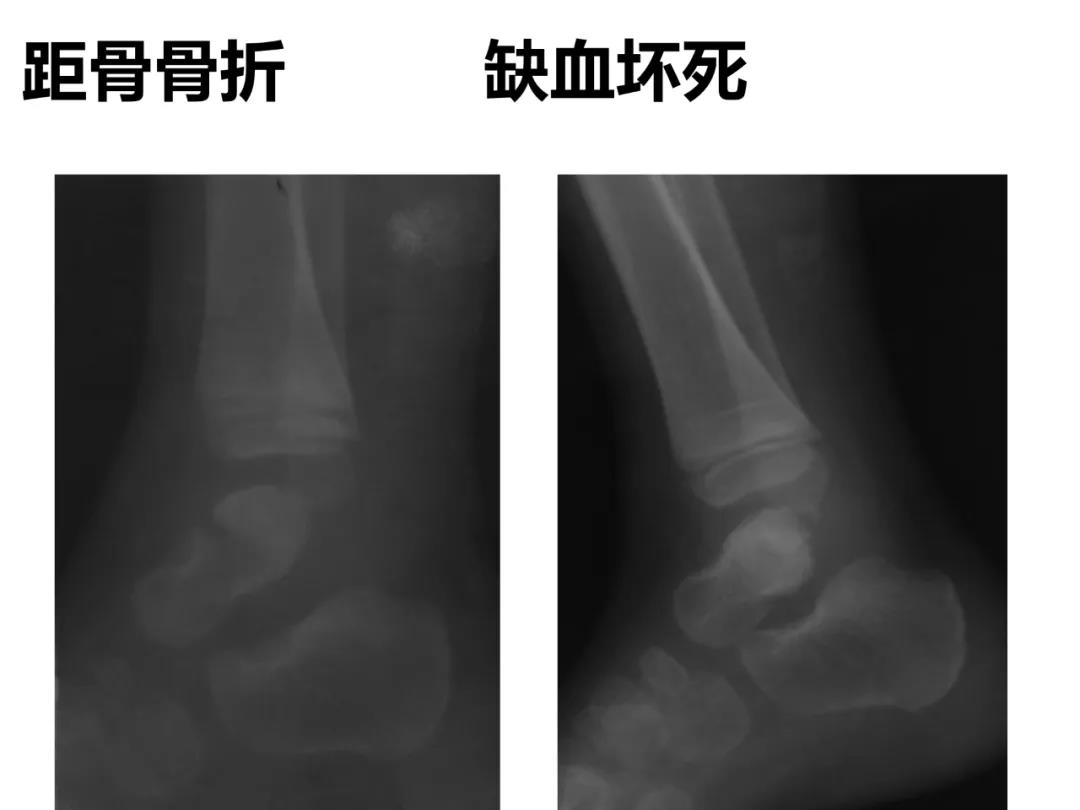

小儿骨科X线片汇总,临床读片宝典!